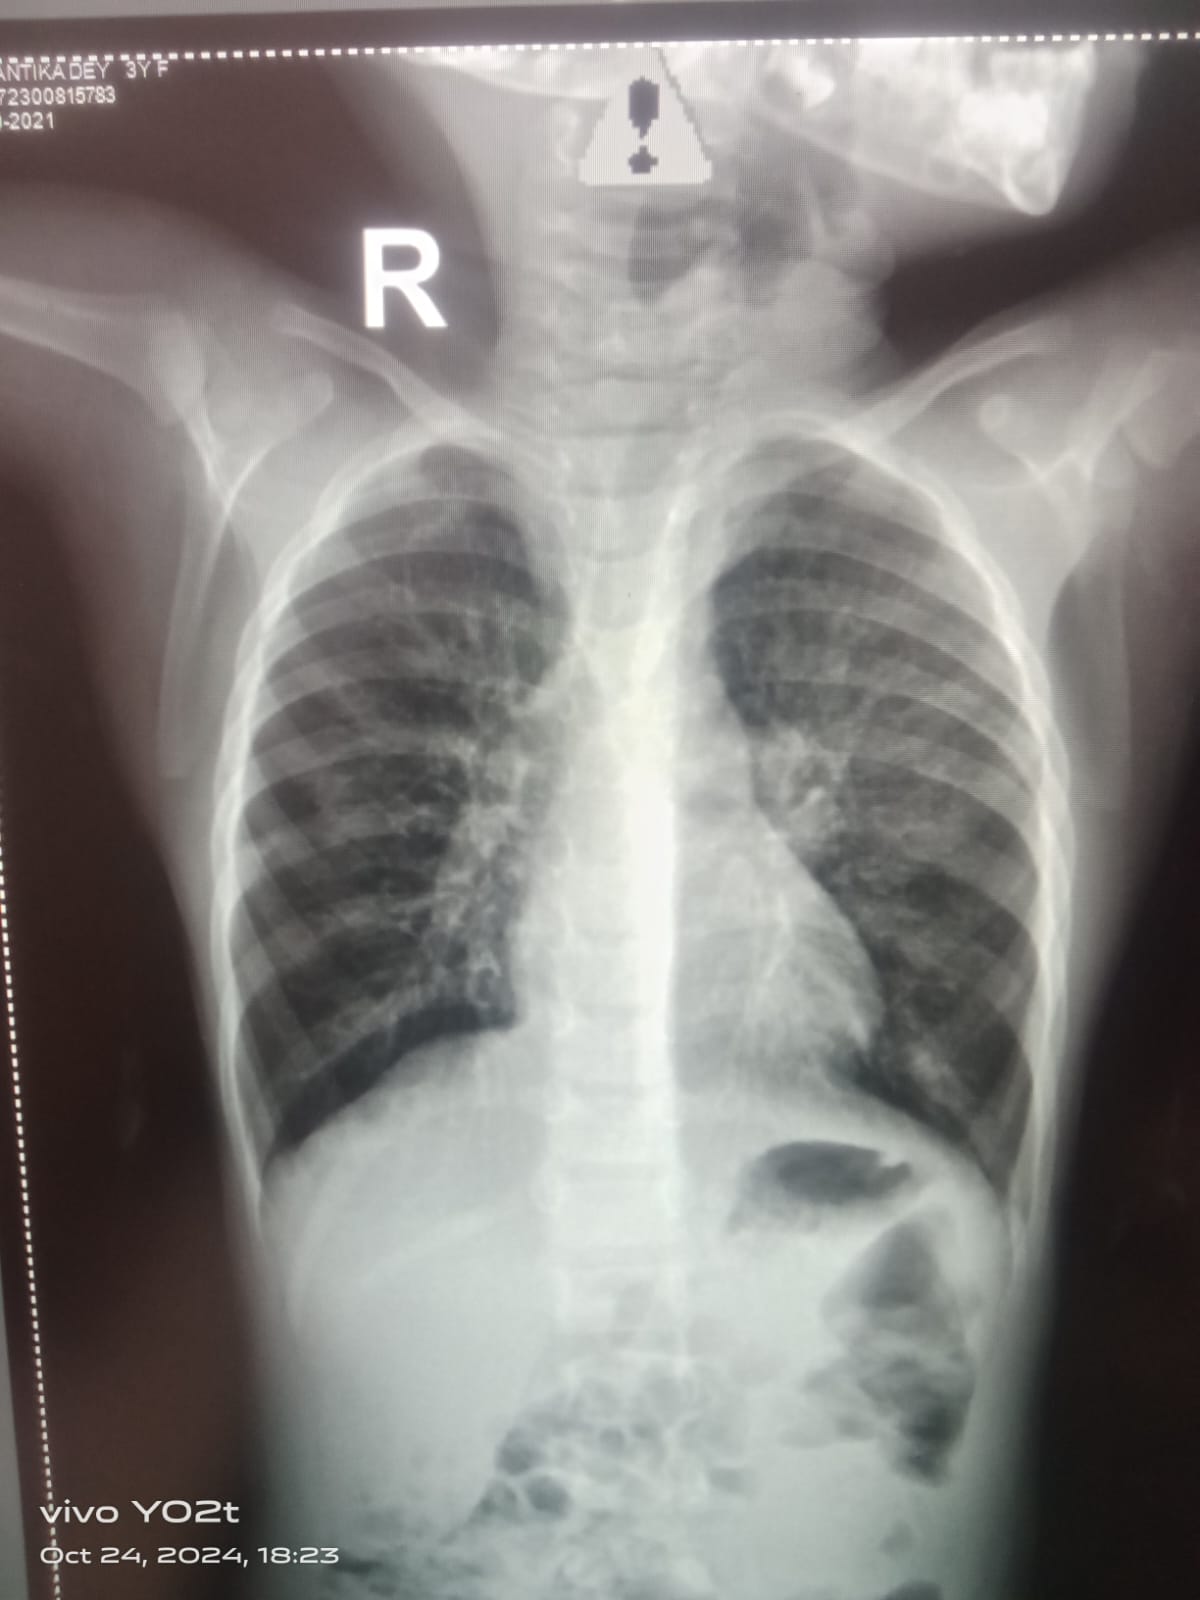

Current Case